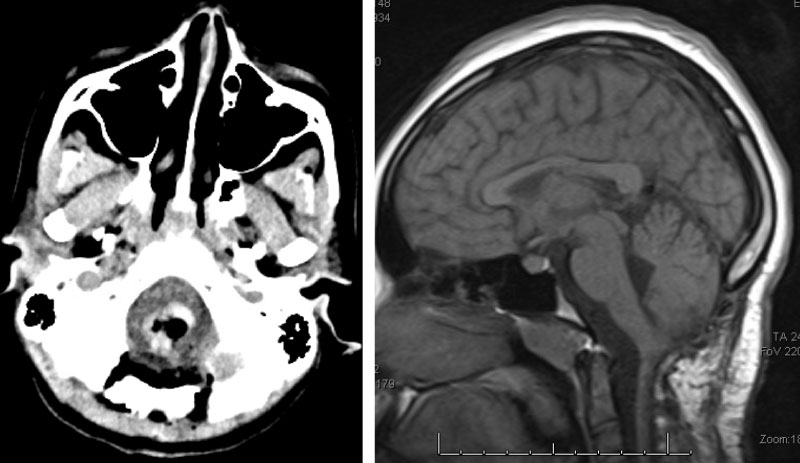

Following, the intramedullary brainstem tumor was successfully resected via suboccipital craniotomy and upper cervical laminectomy. The patient did well after surgery.

Five years following surgery, the patient is fully recovered, and is a thriving high school senior.

Figure 3. Immediate post-op CT (left) and two-year follow-up MRI (right).